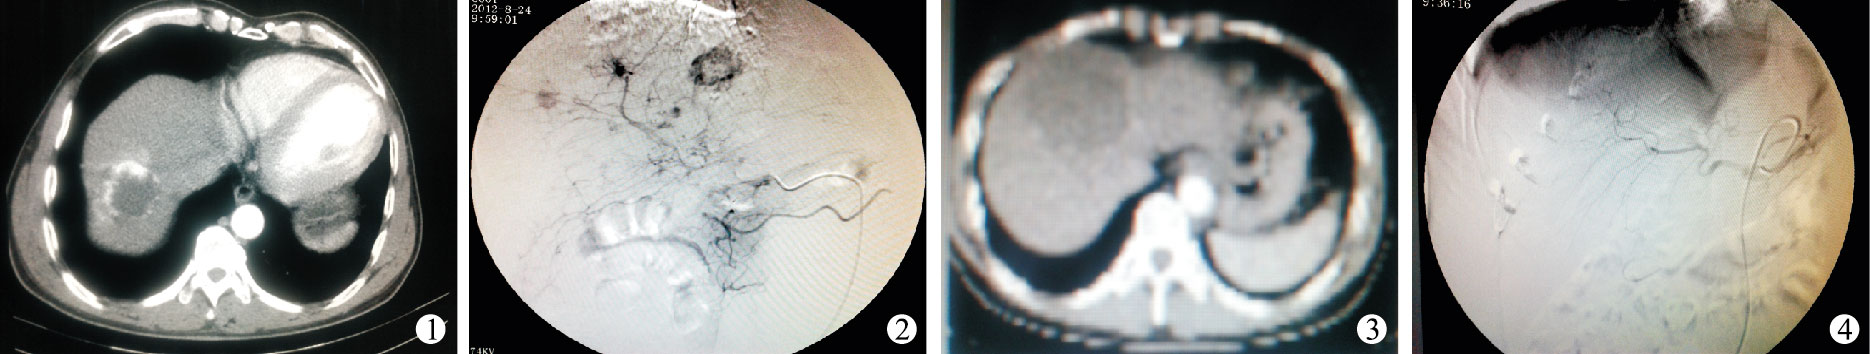

富血竇、富血供型CHL患者71例,CT增強掃描動脈期邊緣呈多發結節狀強化或動脈早期整個病灶填塞強化,呈富血改變(圖 1);動脈造影顯示肝動脈及主要分支增粗扭曲,見多個大小不等的血竇顯影,呈“樹上掛果”征象和“爆米花”樣染色,周圍血管湖可呈“環形”、“弧形”等征象,造影劑滯留呈“早出晚歸”現象,病灶大部分或全部由大小不等豐富血竇充盈(圖 2)。少血竇、乏血供型CHL患者15例,CT增強掃描動脈期邊緣呈點狀強化或輕度邊緣強化,呈乏血供改變(圖 3);動脈造影顯示病灶呈“樹上掛果稀少”征象,無明顯周圍血管湖顯影,病灶邊緣少量、零散異常血竇充盈(圖 4)。CT增強掃描動脈期血管瘤強化血供特點與動脈造影動脈期血管瘤異常血竇充盈多少表現基本一致。